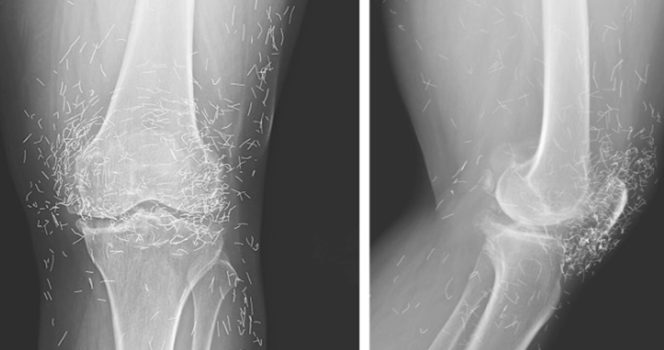

Cuando una mujer surcoreana de 65 años acudió al médico por un dolor en la rodilla, los médicos no esperaban encontrar un tesoro. Pero eso fue precisamente lo que encontraron.

Así que recurrió a la acupuntura, según un caso publicado en la revista New England Journal of Medicine.

La acupuntura, un tratamiento con siglos de antigüedad en países como China, consiste en insertar agujas en puntos específicos del cuerpo para aliviar el dolor o tratar enfermedades. En este caso, las agujas, presumiblemente de oro, se dejaron intencionadamente en sus rodillas para continuar con la estimulación.

También advirtió que las agujas incrustadas pueden complicar las lecturas de rayos X. «Las agujas pueden ocultar parte de la anatomía», dijo Guermazi en 2013.